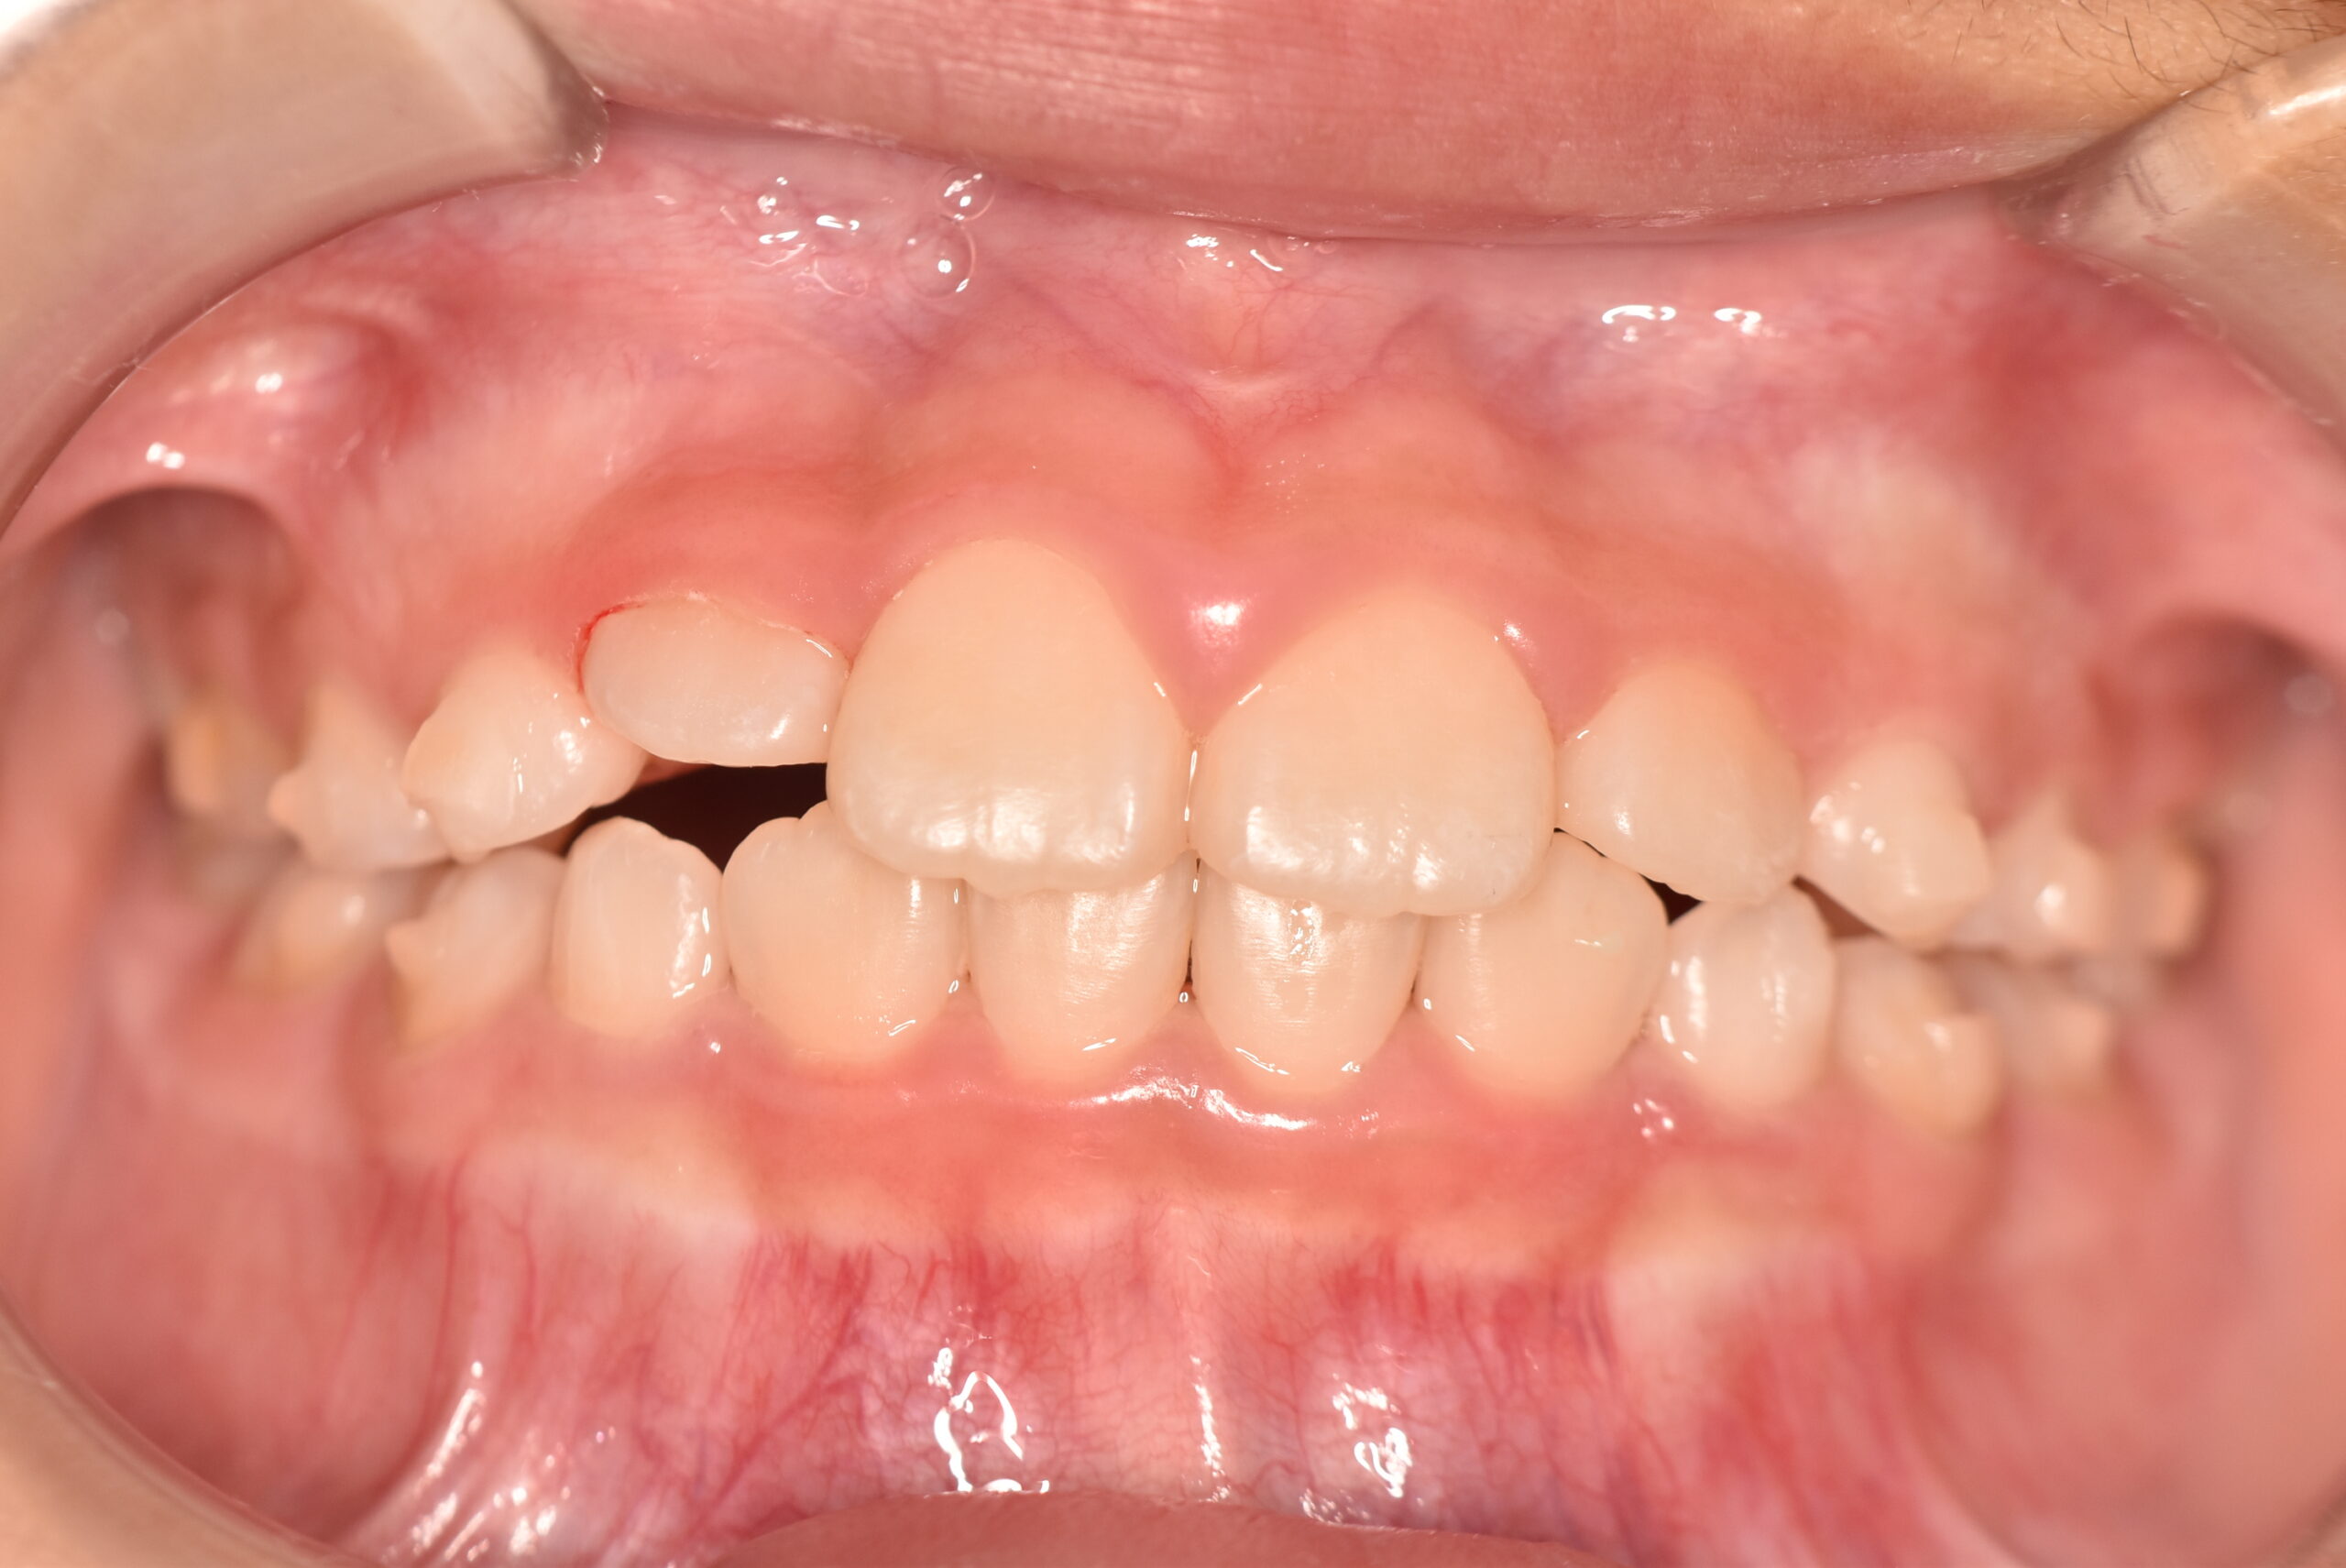

動的治療終了時

症例 症例 症例 症例

治療としてはマウスピース矯正(インビザラインファースト)で配列を行い、上下顎の側方拡大と萌出スペースを確保しました。

治療期間は、7ヶ月でした。

今後、側方歯生え変わりまで経過観察を行います。